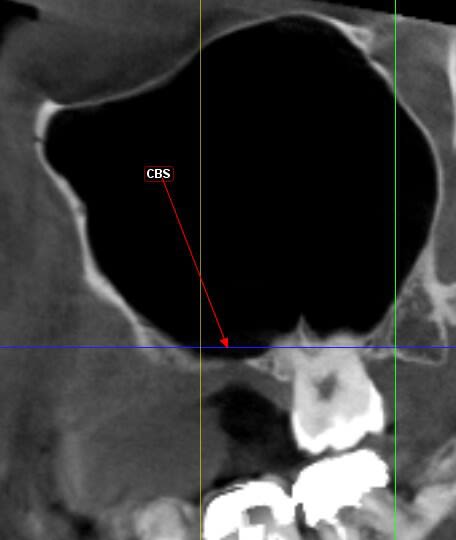

je dois pratiquer un rehaussement de plancher sinusien par volet latéral et je ne sais comment gérer le décollement de la membrane de Schneider au niveau de la communication bucco sinusale

Dès le départ, je m'inquiète au niveau du décollement du lambeau sur la CBS, on risque de déchirer à ce moment là

je joins quelques captures pour vous faire une idée

vos avis éclairés sont les bienvenus

je ne vois pas de septum dans la zone de comblement

pourrais-tu préciser?